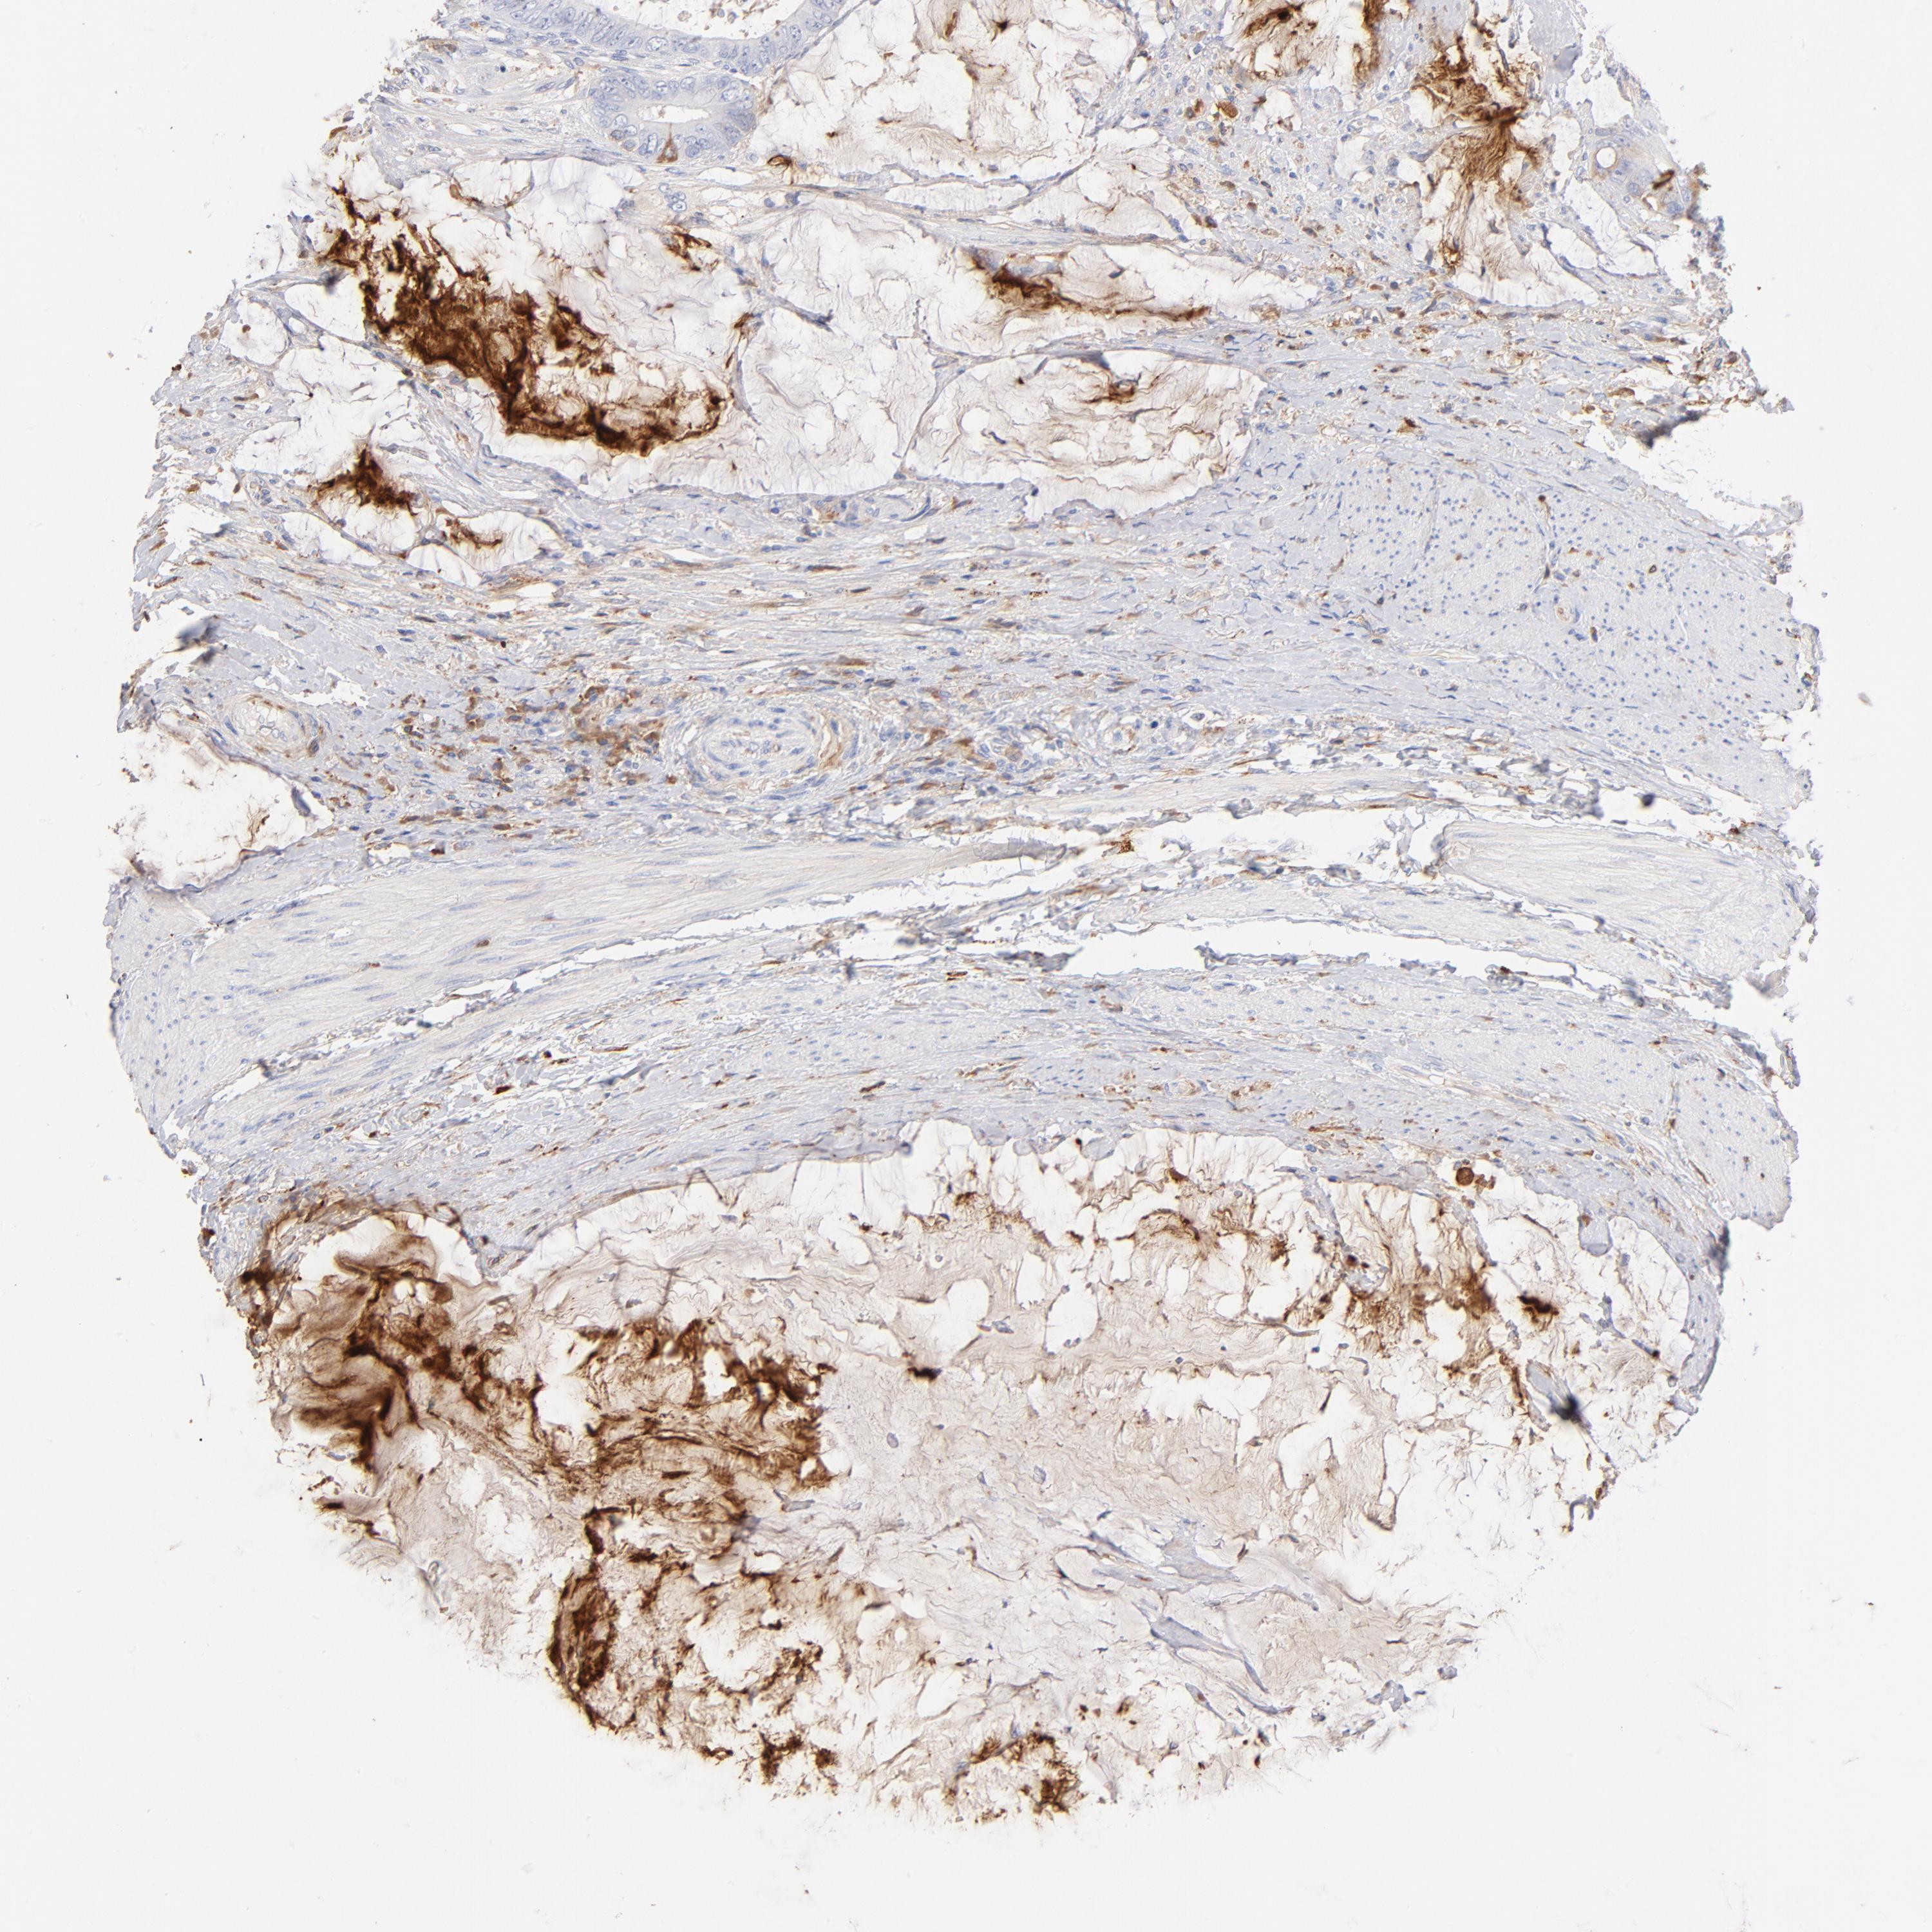

CANCER COLORECTAL CANCER Show tissue menu

Colorectal cancer

Human cancer

Rectum adenocarcinoma